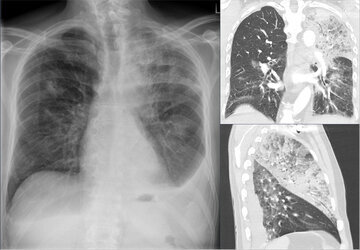

Дамы чаще сталкиваются с ее нежелательными последствиями. Например, у них быстрее развивается жесткость сосудов, увеличение размеров сердца. Что нередко приводит к инсульту или сердечной недостаточности.